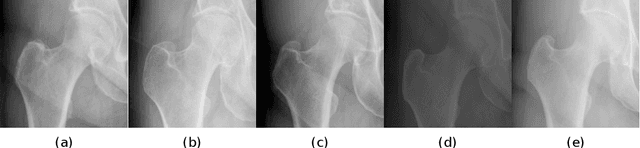

Accurate segmentation of anatomical structures is vital for medical image analysis. The state-of-the-art accuracy is typically achieved by supervised learning methods, where gathering the requisite expert-labeled image annotations in a scalable manner remains a main obstacle. Therefore, annotation-efficient methods that permit to produce accurate anatomical structure segmentation are highly desirable. In this work, we present Contour Transformer Network (CTN), a one-shot anatomy segmentation method with a naturally built-in human-in-the-loop mechanism. We formulate anatomy segmentation as a contour evolution process and model the evolution behavior by graph convolutional networks (GCNs). Training the CTN model requires only one labeled image exemplar and leverages additional unlabeled data through newly introduced loss functions that measure the global shape and appearance consistency of contours. On segmentation tasks of four different anatomies, we demonstrate that our one-shot learning method significantly outperforms non-learning-based methods and performs competitively to the state-of-the-art fully supervised deep learning methods. With minimal human-in-the-loop editing feedback, the segmentation performance can be further improved to surpass the fully supervised methods.